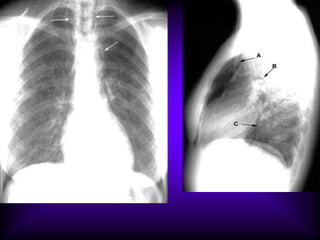

Squamous Cell Carcinoma Lung

LUL mass

Thick walled cavity

Eccentric location of cavity

Fungous Ball

Long standing cavity

Containing round density (A)

Mobile density

Adjacent pleural reaction (B) - characteristic of aspergilloma